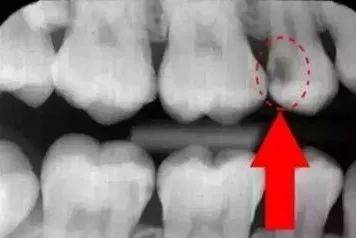

下图圈出来的地方或多或少都有点龋齿,但是有些你并不能看见。这些龋齿还浅不会让你有什么感觉,顶多吃东西塞牙,和冷水敏感而已。

每颗牙都有所龋坏

暗的部位说明龋齿已经非常严重了!

龋坏接近牙髓了